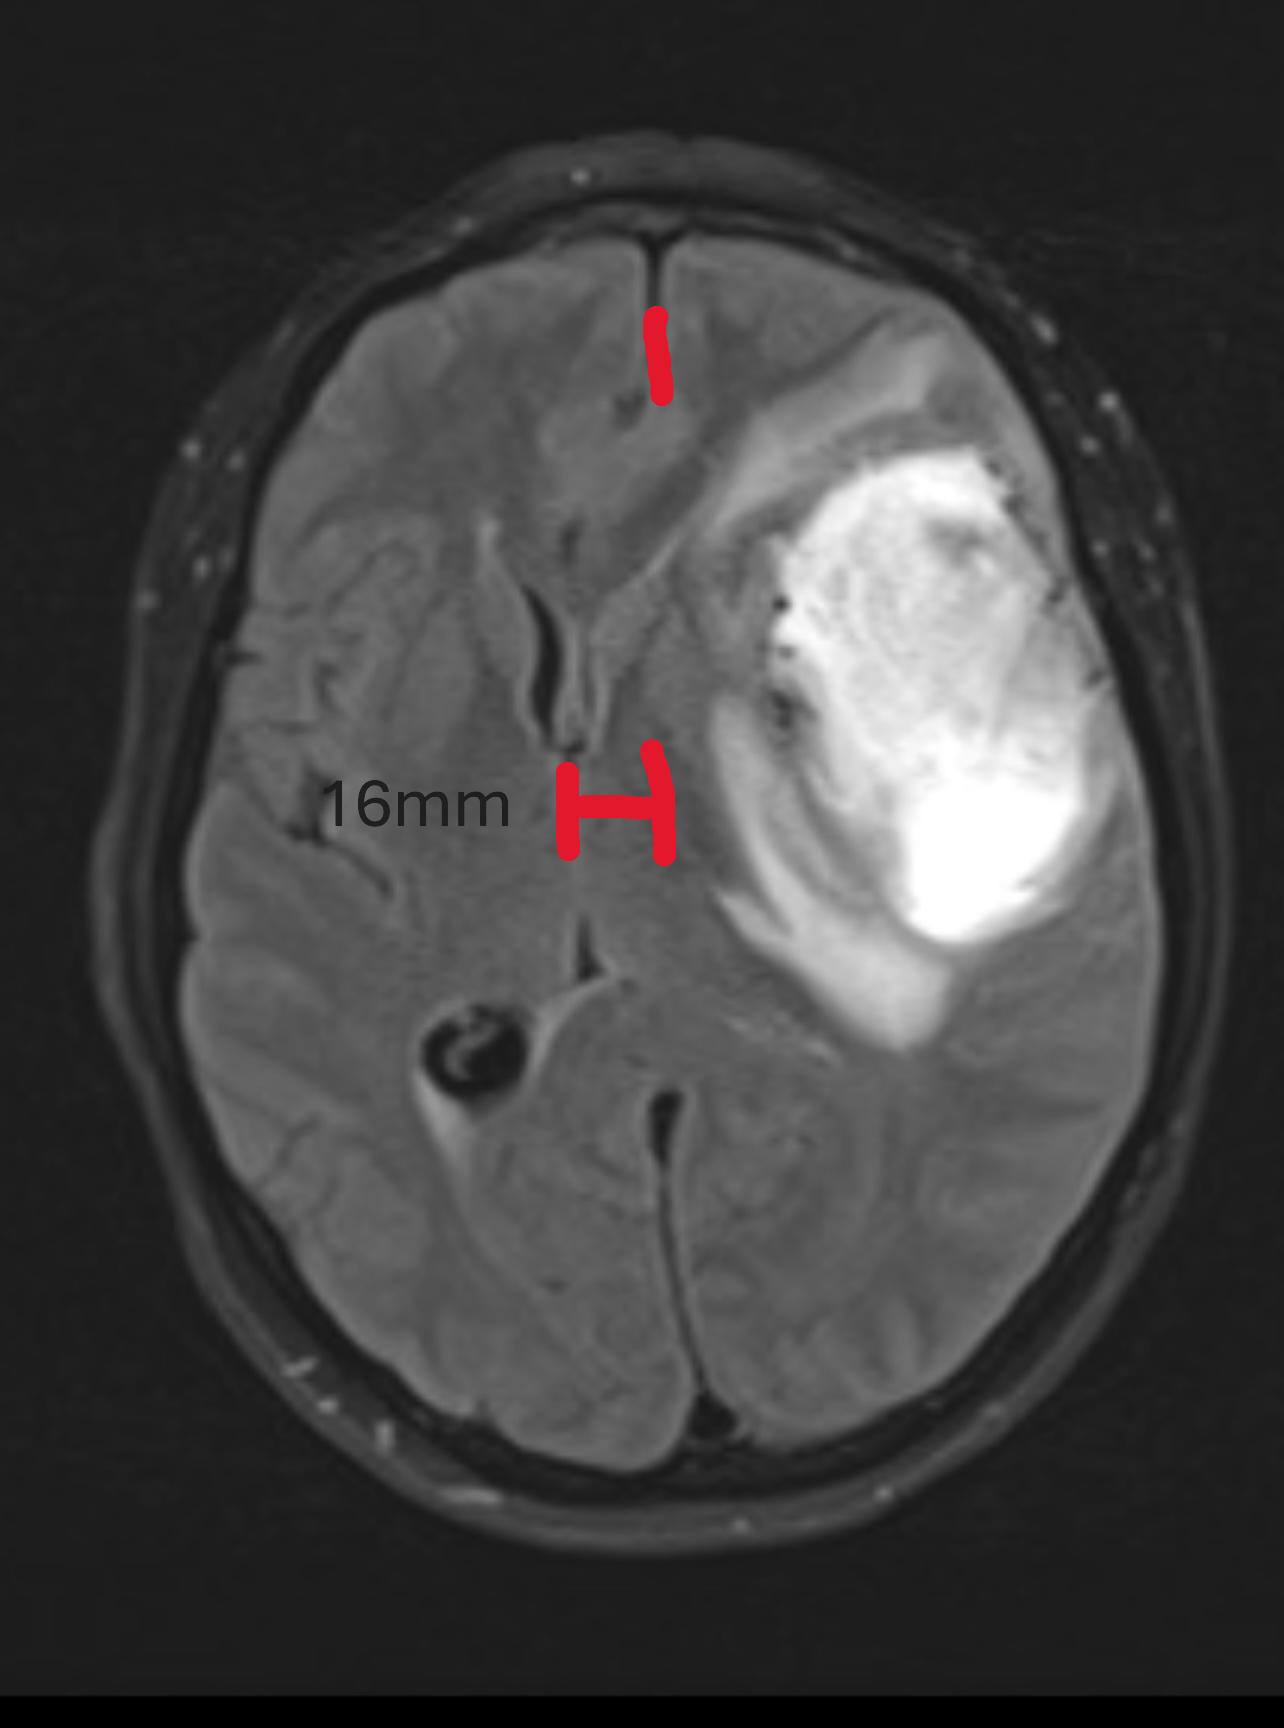

But I am forever the optimist, and I love spreading good news. So, here it is: the spot is GONE! Looking below at the image is a comparison of the October MRI (right pane) with the March one (left pane), an lo-and-behold the spot is nearly gone.

What does this mean? Well, according to the written report of the follow-up visit with the oncologist, this constitutes “remission“. There are no new indications of tumor growth and even the injuries from the treatment are now fading away to nothing.